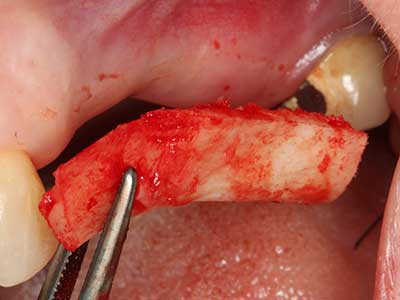

Fig. 3: la separazione basale del blocco è più semplice con i raccordi appositamente angolati.

Fig. 4: mediante l'ablatore osseo si raccolgono ulteriori microframmenti dell'osso autologo.